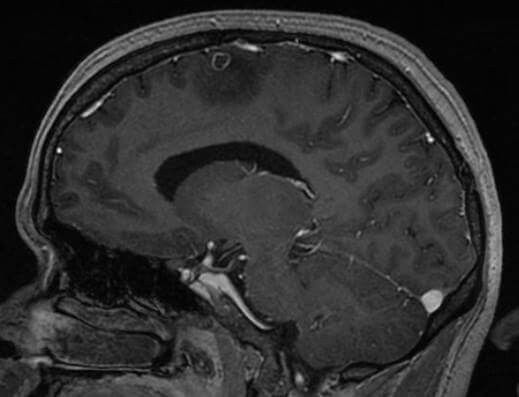

Pada pemeriksaan magnetic resonance imaging (MRI) kepala, didapatkan tumor berukuran 4×2,3×2,1 cm yang mengelilingi ventricular drain. Massa tampak isointense pada T1 dan hypointense pada T2. Massa tampak menyangat kontras secara heterogen. Pada dynamic susceptibility contrast (DSC) MRI perfusion dan MR Spectroscopy (MRS) mendukung ke arah proses keganasan. Tidak didapatkan gambaran meningoensefalitis. Dari hasil pemeriksaan MRI kepala mendukung ke arah proses metastase dari kraniofaringioma.